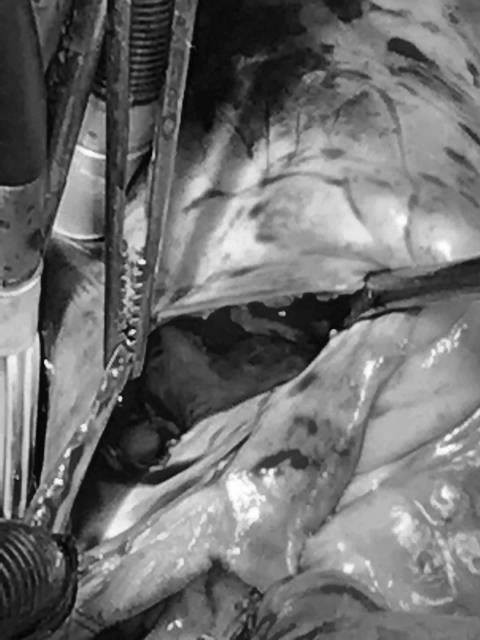

16/04/2019 16:52Kỳ lạ cô gái mắc tim bẩm sinh có phủ tạng đảo ngược được cứu sống ngoạn mục

Bệnh nhân Trần Thị Mai Ngoan (26 tuổi, ở Thành phố Thanh Hóa) phát hiện bệnh tim bẩm sinh từ lúc 3 tuổi. Bệnh nhân cho biết đã đi khám ở nhiều nơi nhưng không phẫu thuật được. Trước đó, người phụ nữ này đã từng bị thai lưu.

Bệnh nhân đến khám tại Bệnh viện Tim Hà Nội, các bác sĩ chẩn đoán bệnh nhân bị tim bẩm sinh thể rất nặng – đảo gốc động mạch có sửa chữa kèm theo hẹp nặng van động mạch phổi.

TS.BS Nguyễn Sinh Hiền – Phó Giám đốc Bệnh viện Tim Hà Nội cho biết, ở bệnh nhân này, nhĩ phải nối với thất trái đi lên động mạch phổi, còn nhĩ trái nối với thất phải và đi lên động mạch chủ.

Ngoài ra bệnh nhân có lỗ thông liên thất rất lớn, thêm vào đó bệnh nhân bị ngược phủ tạng, tức là gan nằm bên trái còn dạ dày nằm bên phải.

Chia sẻ về quá trình phẫu thuật ở ca bệnh đặc biệt này, TS.BS Nguyễn Sinh Hiền cho biết: “Chúng tôi phải vá lỗ thông liên thất, phải chuyển vị cả tầng nhĩ và tầng thất, phải cắt cả động mạch chủ, động mạch phổi, động mạch vành; đồng thời đảo lại. Ngoài ra tầng nhĩ chúng tôi cũng phải đảo lại và dùng một ống mạch nhân tạo…”.

“Bệnh nhân này có cái khó là bệnh nhân bị ngược vị tạng, trong quá trình phẫu thuật bác sĩ phải đứng bên trái bệnh nhân, tất cả tổn thương phải làm ở bên trái nên khả năng thao tác rất khó khăn, bác sĩ phải “tượng tượng” thật tốt thì mới “sửa chữa” cho ca mổ thành công được”- chuyên gia tim mạch cho hay.

Sau phẫu thuật, bệnh nhân cho biết tình trạng sức khỏe tốt hơn rất nhiều, trái tim đã ổn định.

TS.BS Nguyễn Sinh Hiền cho biết, phương pháp phẫu thuật ccTGA này đã được tiến hành ở những nước có nền phẫu thuật tim phát triển, áp dụng cho những trường hợp bệnh nhân bị tổn thương hoán vị đại động mạch có sửa chữa, là những tổn thương rất phức tạp. Thời gian cho một ca mổ thường kéo dài từ 7 đến 8 tiếng đồng hồ.

Theo các bác sĩ, ở Việt Nam, hiện tại, những ca phẫu thuật như thế này vẫn chưa nhiều. Đây cũng là ca phẫu thuật ccTGA đầu tiên được tiến hành tại Bệnh viện Tim Hà Nội. Điều này sẽ mở ra nhiều cơ hội cho các bệnh nhân tim bẩm sinh với những tổn thương phức tạp được điều trị hiệu quả trong thời gian tới.